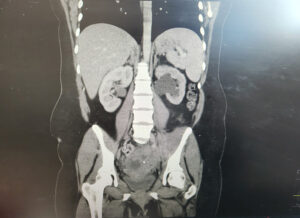

A 32-year-old para 4 woman presented with severe abdominal pain. Laboratory results showed hemoglobin 71 g/L, white cell count 15.4 × 10⁹/L, and C-reactive protein 236 mg/L. She received intravenous co-amoxiclav and metronidazole, along with oral doxycycline.

CT imaging revealed a complex cystic lesion in the pouch of Douglas with involvement of the left ureter and hydroureteronephrosis (Figure 3). MRI confirmed a left TOA with associated iliopsoas myositis and posterior cervical wall invasion (Figure 4). Ultrasound-guided drainage was attempted but was unsuccessful because of adjacent bowel loops. A ureteric stent was inserted, followed by laparoscopic drainage of the abscess (500 mL of pus) and right cystectomy with adhesiolysis. She was tested for tuberculosis and HIV, both of which were negative. She recovered well and was discharged four days postoperatively, with planned ureteric stent removal at follow-up.